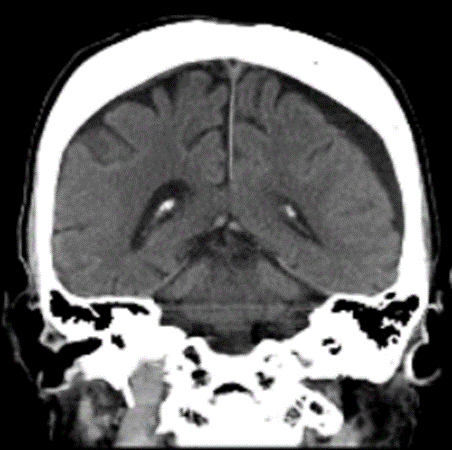

穿頭(せんとう)血腫除去術後

血腫は除去されている

術後から症状は改善され、退院。